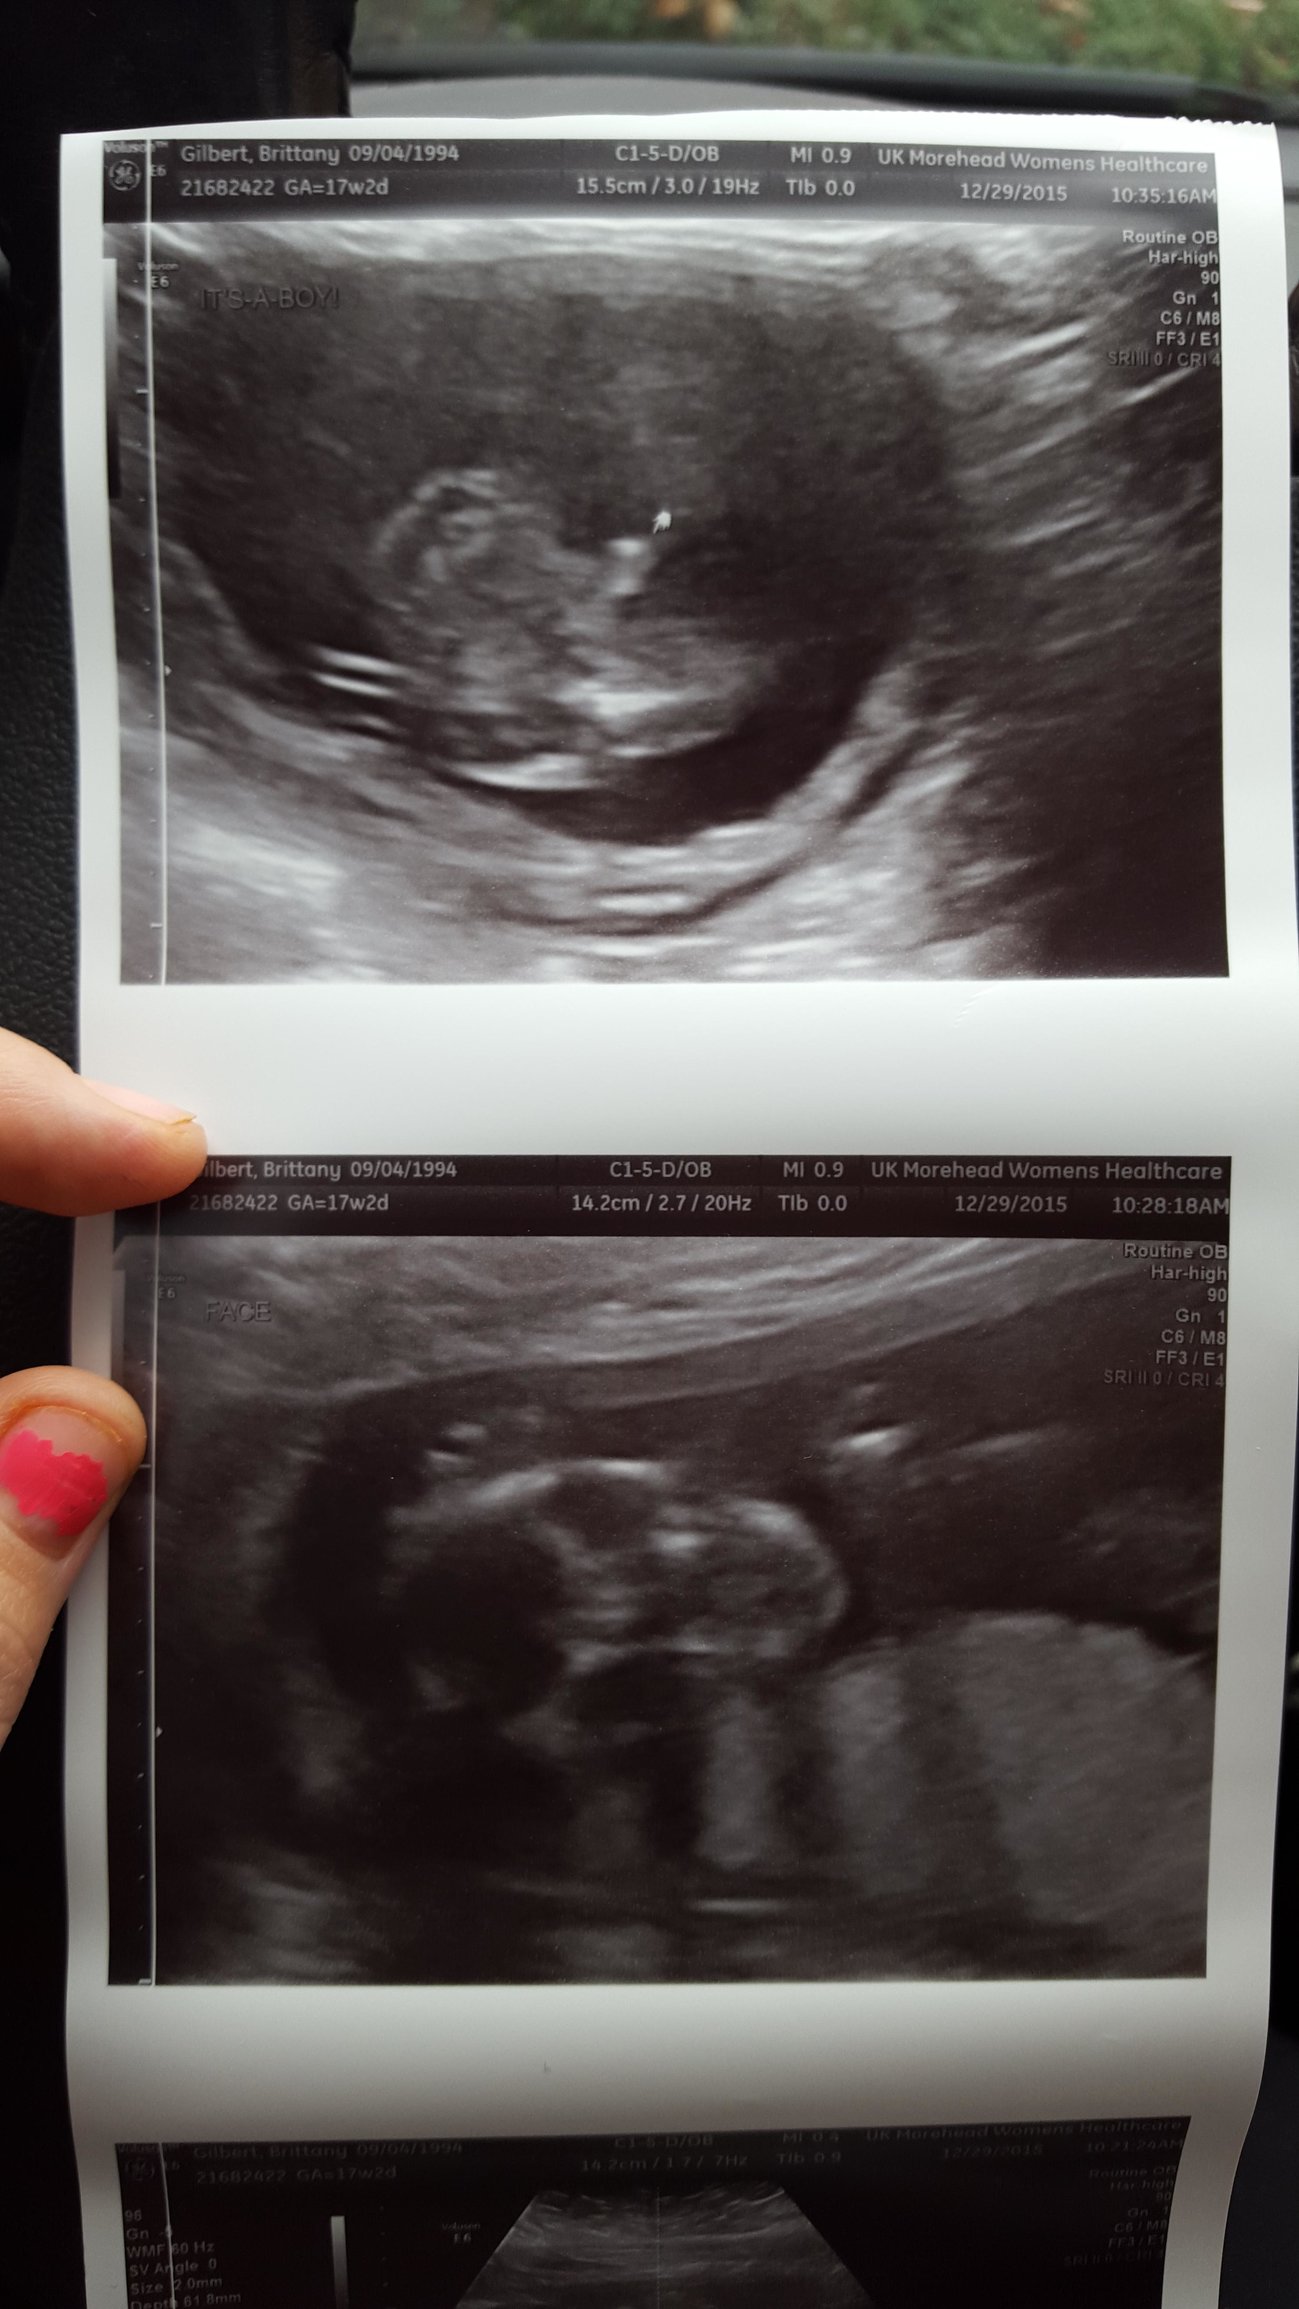

I'm freaking out right now. I'm seeing another face in my ultrasound. Can somebody please explain to me what this could be or am I really having twins. I didn't notice this until I got home!!

• I read somewhere that it's some kind of mirror image type thing caused by the ultrasound technology. I think if it was twins your doctor would ha e said that!

• Looks like a mirror image of your baby's face. You would definitely see another fetus if it was there.

• Yeah I was 17 weeks 2 days when they took these. It just had me freaked out. I didn't notice it till I got home and my mom actually pointed it out to me. But thanks for your feedback guys it is aprechiated!

• i dont see another face anywhere on the scan. then again, I'm not a US tech. if you were having twins, the tech would have told you. you're far enough along that they would be able to tell.

• You would be able to see twins really clearly by now and usually from that angle (if you saw anything from the twin) you'd see a foot, arm or leg. What you're seeing could be any number of things but if it was something to worry about your tech or your doctor would say something.